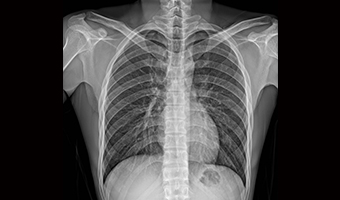

Uygulama Görüntüleri

Tam Boyut